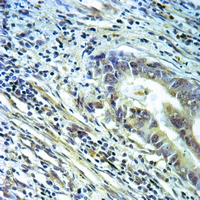

Immunohistochemical analysis of Annexin A2 staining in human brain formalin fixed paraffin embedded tissue section. The section was pre-treated using heat mediated antigen retrieval with sodium citrate buffer (pH 6.0). The section was then incubated with the antibody at room temperature and detected using an HRP conjugated compact polymer system. DAB was used as the chromogen. The section was then counterstained with haematoxylin and mounted with DPX. -